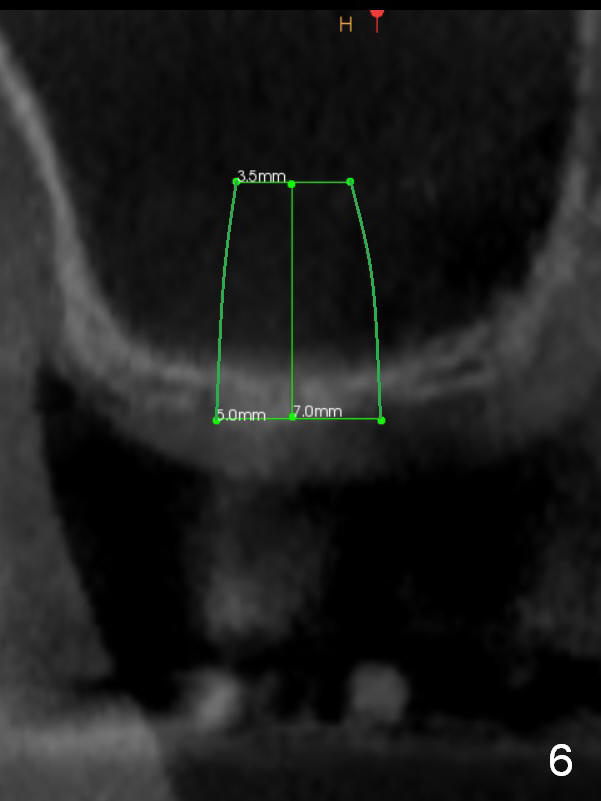

A 78-year-old man needs implant restoration at #2 in spite of limited bone height, because of severe ridge atrophy at #18 and 19. Sagittal (Fig.1-3) and coronal (Fig.4-6) sections show bone height less than 1 mm. If there is plenty of the keratinized tissue at #2, use a 4 mm tissue punch for access, followed by sinus lifter. Use fine and coarse allograft for sinus lift.